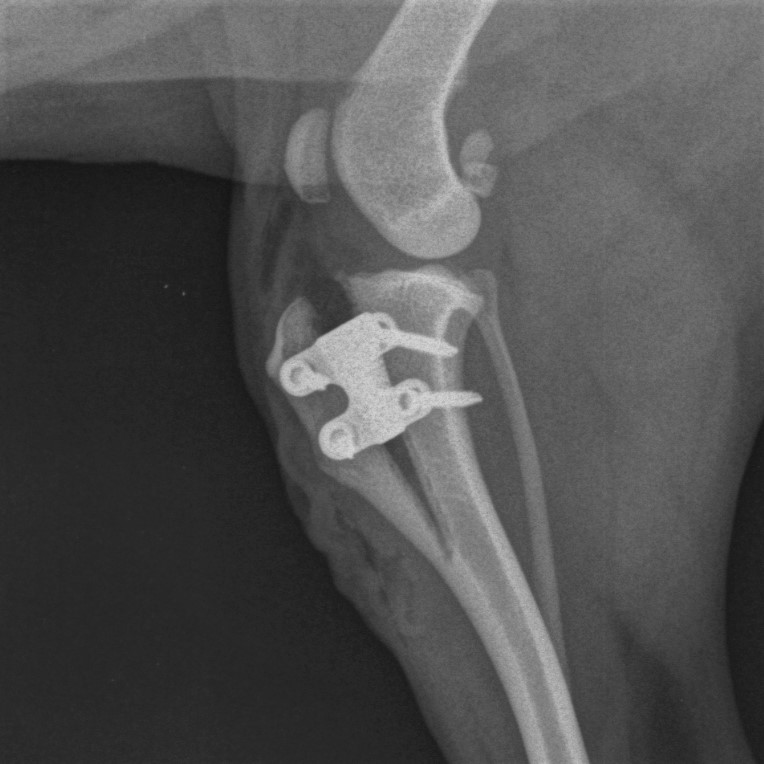

Tra le tecniche oteotomiche ricordiamo la TPLO (tibial plateau leveling osteotomy), la TTA (tibial tuberosity advancement), la TTO (triple tibial osteotomy), ecc. Queste osteotomie correttive trasformano le forze di scivolamento tra tibia e femore in forze di compressione annullando così il movimento tra le due ossa (lavoro che fisiologicamente svolge il legamento crociato integro). Questi tipi di interventi riducono le complicanze sia nel breve che nel medio-lungo periodo, dando una maggiore stabilità articolare e riducendo la formazione di artrosi di ginocchio.

All’interno del mio ambulatorio viene eseguito l’intervento di TTA-rapid. Questo intervento, in uno studio, ha dato risultati soddisfacenti nel 99% dei casi già dopo 3 mesi e nell’86% dei casi dopo 16 mesi.